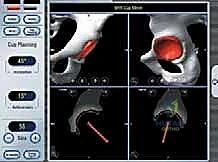

تعتبر هذه الجراحة من أدق جراحات العظام، ويقوم بها الأستاذ الدكتور محمد هطيف بخطوات منهجية دقيقة تضمن أعلى معدلات النجاح:

3. نحت وتشكيل رأس عظمة الفخذ

بدلاً من قطع الرأس، يستخدم الجراح أدوات ميكروسكوبية ومثاقب دقيقة جداً لإزالة الغضروف التالف وطبقة رقيقة من العظم المريض، ليتم "نحت" رأس العظمة ليصبح جاهزاً لاستقبال الغطاء المعدني بشكل مثالي.

4. تركيب الغطاء المعدني (Femoral Component)

يتم تثبيت التاج أو الغطاء المعدني الأملس فوق رأس عظمة الفخذ المنحوت، وغالباً ما يتم تثبيته باستخدام مادة أسمنتية طبية خاصة لضمان ثباته المطلق.

5. تحضير وتلبيس تجويف الحُق (Acetabular Component)

يتم تنظيف تجويف الحوض (الحُق) من الغضاريف المتآكلة باستخدام مبشرة طبية، ثم يزرع وعاء معدني (Cup) داخل التجويف. هذا الوعاء يثبت عادة عن طريق الضغط (Press-fit) حيث ينمو العظم الطبيعي لاحقاً حوله ليثبته بقوة.